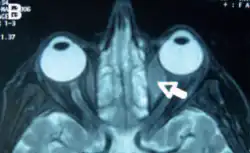

Orbital lymphoma is a common type of non-Hodgkin lymphoma that occurs near or on the eye. Common symptoms include decreased vision and uveitis. Orbital lymphoma can be diagnosed via a biopsy of the eye and is usually treated with radiotherapy or in combination with chemotherapy.